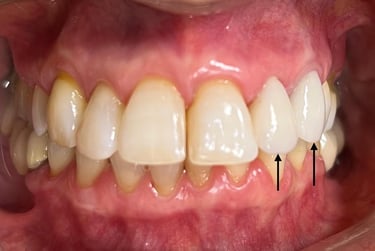

Coroas em Dissilicato de Lítio

Todos os caso a seguir estão associadas a clareamento dentário

Cirurgia de aumento de coroa clínica antes das coroas

Caso que demonstra a vantagem da integração de diversas áreas da odontologia, unindo cirurgia, periodontia, prótese e estética para alcançar resultados funcionais e harmônicos.

Antes

Depois